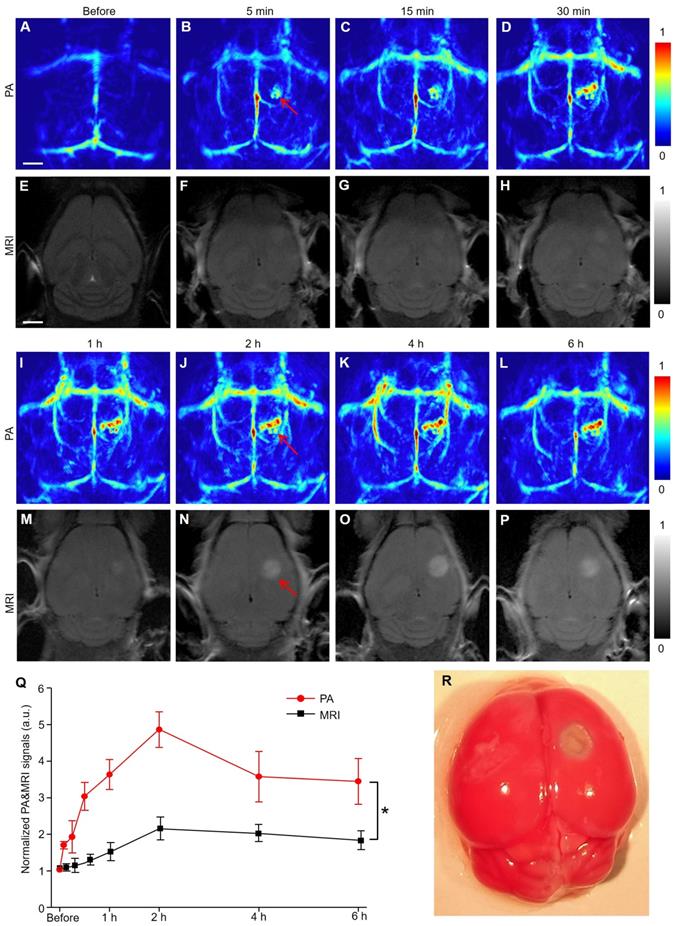

PACT and MRI were simultaneously employed to detect the infarct area at different time points (Figure 1). Five minutes after EB dye injection, we observed an area with a significantly increased PA signal (indicated by a red arrow in Figure 1B). The area gradually expanded over time and formed a caterpillar-like shape (indicated by a red arrow in Figure 1J). The PA signal intensity in this region increased rapidly within 2 h and gradually decreased over time to reach a plateau (Figure 1Q). The viable tissue was stained red and the non-viable infarct tissue remained white following triphenyl tetrazolium chloride (TTC) staining of the mouse brain (Figure 1R and S4), showing excellent consistence with our PA observations. Furthermore, the microscopic images of brain tissue slices (H&E staining) revealed different pathological manifestations in both infarcted and non-infarcted areas. In the infarcted area, the numbers of nerve cells decreased and were irregularly located. Vacuoles formed in the cytoplasm with obvious interstitial enlargement and nuclear pyknosis (Figure S5). Therefore, we concluded that the noticeable PA signal changes indicated the infracted area.

Figure 1

PACT and MRI of mouse brain in a photothrombosis model at an early stage in vivo. (A-D), (I-L) Representative PA images of a photothrombosis mouse model right followed by EB dye injection at varied time points upon injection at 680 nm. (E-H), (M-P) Representative MR images of a photothrombosis mouse model at varied time points. (Q) Normalized PAI and MRI signals of mice brains (n = 5; the error bars show the standard deviation) in infarcted areas at varied time points upon EB dye injection. (*) P < 0.05. (R) Triphenyl tetrazolium chloride staining in the brain of model mice. Scale bar, 1 mm.

Representative MR images at the corresponding time points after IS of mice model (Figure 1E-H, M-P) showed that the signal of the infarct location was almost negligible within the first hour and difficult to identify until after 2 hours. By quantifying the signal value of the infarct area, PACT had a much stronger signal-to-background ratio (approximately twofold) than the MR image in Figure 1Q (P < 0.05). The time of data acquisition was 1.7 min for PAI in contrast to 5 min for MRI. In summary, PACT allowed the dynamic observation of the infarct area with the prolongation of ischemic time. Furthermore, PACT could detect the infarct area at a much earlier stage than conventional MRI in this study (5 min versus 2 h) with a faster imaging time (1.7 min versus 5 min).